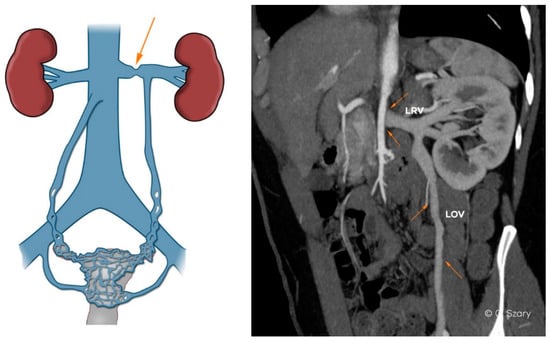

| - absence or (partial) hypoplasia of LRV (Figure 4) |

| - distended ostium of the LOV draining into the LRV |

| - lack of an ostial or subostial valve in the LOV trunk |

| - atypical LOV drainage (the most frequent form draining into the main branch of LRV) |

| - combined anatomy of the LOV system (e.g., duplication of the main trunk) |